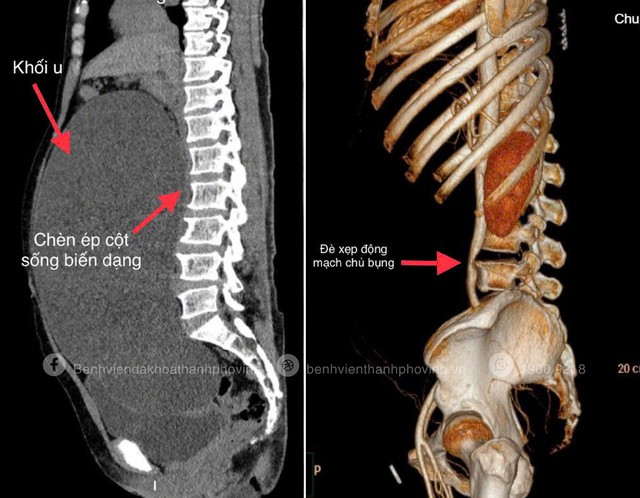

Hình ảnh khối u nang buồng trứng khổng lồ chiếm trọn ổ bụng, chèn ép gây xẹp động mạch chủ bụng, các cơ quan bị đẩy lệch vị trí, niệu quản bị ép gây giãn đài bể thận hai bên.

Tại đây, các bác sĩ bất ngờ khi thấy bụng người bệnh phình to, căng cứng như phụ nữ mang thai 8 tháng. Kết quả chụp CT-Scanner 256 lát cắt cho thấy một khối u nang buồng trứng khổng lồ chiếm gần toàn bộ ổ bụng, chèn ép làm xẹp động mạch chủ bụng, đẩy lệch nhiều cơ quan, ép niệu quản gây giãn đài bể thận hai bên và thậm chí làm biến dạng cột sống.